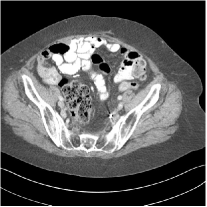

III.C.2. Simulation Framework, Reconstruction Results, and Comparisons

The synthesized low-dose clinical measurements are simulated from regular-dose images at a resolution of mm with a fan-beam CT geometry corresponding to a monoenergetic source at incident photon intensity . The sinograms are of size . The width of each detector column is mm, the source to detector distance is mm, and the source to rotation center distance is mm. We reconstruct images of size with the pixel size being mm mm.

We conducted experiments on one test slice used for parameter tuning (L067-slice 120) and four independent test slices (L109-slice 90, L192-slice90, L333-slice140, L506-slice 100) of the Mayo Clinic data. For PWLS-EP, we ran iterations using relaxed OS-LALM and set regularization parameter . We used the same as the phantom experiments for Algorithm 2. The process of selecting a general set of reconstruction parameters () for the Mayo Clinic test slices is identical to that for the XCAT phantom in Section III.B.2. The selected regularization parameter and the parameters that control the sparsity of the coefficient maps are for ST, , , , , for MARS2, , , , , , , for MARS3, , , , , , , , , , , for MARS5, and , , , , , , , , , , , , , , for MARS7, respectively.

Figs. 8, 9, 10, and 11 show the reconstructions of the four independent slices using the FBP, PWLS-EP, PWLS-ST, PWLS-MARS2, PWLS-MARS3, PWLS-MARS5, and PWLS-MARS7 schemes, respectively. Additional Mayo Clinic experimental results of the parameter tuning case (Fig. 15) are shown in the supplementary document. Table 1 lists the RMSE and SSIM values of reconstructions of the four independent test slices, with the best values bolded. Generally, the five and seven layer models provided the best RMSE and SSIM values. They outperform the single-layer model by HU in RMSE on average. However, the MARS5 and MARS7 models perform similarly. In order to strengthen the benefits of the multi-layer model, Table 2 lists the RMSE of the reconstructions in four different ROIs (shown in the reference of Fig. 11) with seven methods for slice 100 of patient L506. By observing the reconstructed images, we see that although the ST model achieves a cleaner reconstruction result than FBP and PWLS-EP, it still sacrifices some sharpness of the central region and suffers from loss of details. The deeper models have a somewhat more positive effect in terms of maintaining subtle features, which is clearly more essential to clinical diagnosis. Furthermore, as we will discuss later, after considerable parameter tuning, we found that the information contained in residual maps is gradually decreased with the number of layers, eventually vanishing at some layer, which suggests that very deep unsupervised models might not offer significantly better image quality.